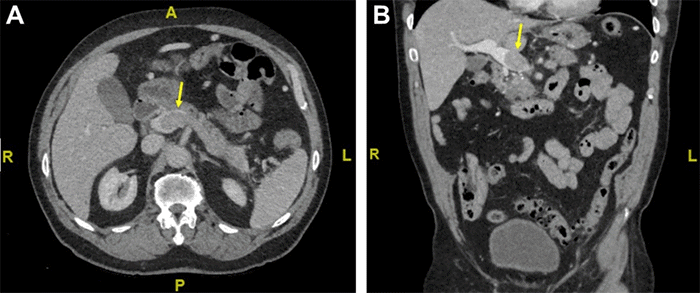

The patient initially presented with an obscure upper gastrointestinal bleed, from which he subsequently recovered, and underwent a diagnostic evaluation. The scan did not reveal the bleeding source but identified a significant mass (6.2 × 3.0 cm) in the tail of the pancreas (Figure 1). Notably, a tumor thrombus was present, completely occluding the splenic vein and extending into the proximal main portal vein. Interestingly, the superior mesenteric vein and arterial supply remained unaffected. Additionally, the CT scan showed no dilation of the biliary or pancreatic ducts, and no signs of distant metastases were observed. These findings raise suspicion for a non-functioning neuroendocrine tumor with associated extensive tumor thrombus.

Figure 1. Axial (A) and Coronal (B) Arterial Phase CT Liver. Published with Permission

Scan depicts a filling defect at the splenoportal confluence, consistent with a tumor thrombus (arrows). The filling defect extends proximally to the level of the inferior mesenteric vein (not visualized in this image)